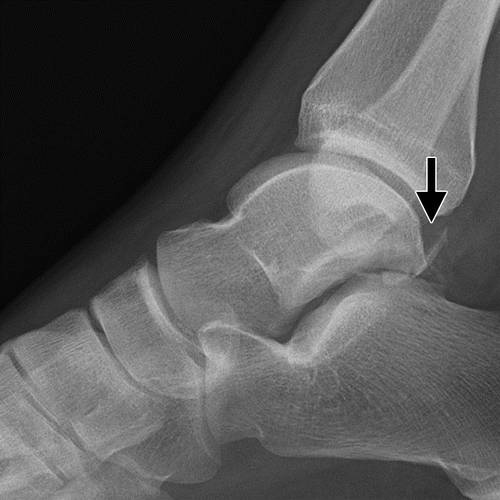

该分类系统是基于与垂直距骨颈骨折的关节排列不齐。 类型I是没有半脱位或脱位的距骨颈的无位移骨折(图5)。 这种类型的裂缝通常难以检测,因为垂直裂缝线可以平行于X射线束。 唯一的距骨血液供应通常涉及这种类型的损伤,都是来自于距骨颈的背侧方面进入椎间孔及近端进步进入人体血管。 剩余的两个血供血源得以保留。

图5 Hawkins-Canale I型距骨颈骨折。 踝关节的矢状CT图像显示通过距骨颈的非置换骨折(箭头)。 注意,骨折前面的后下方小关节面的下延伸,限定了距骨颈部位置。